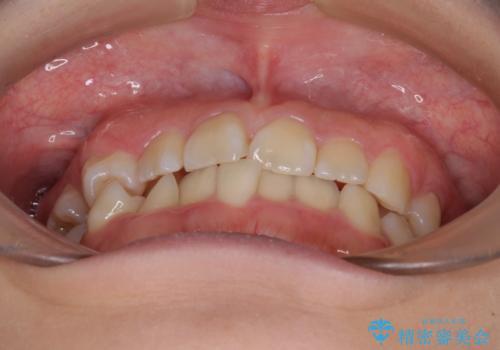

- 内側に生えている歯や埋もれた奥歯を気にして来院された患者様です。

顎の骨が小さいため、歯列が収まりきらずに叢生や未萌出となっている状態でした。

埋もれた奥歯を萌出させ、さらにデコボコを解消するために、上下左右の第1小臼歯4本に加え、親知らず4本も抜歯し、ワイヤー装置にて矯正治療を行うこととしました。